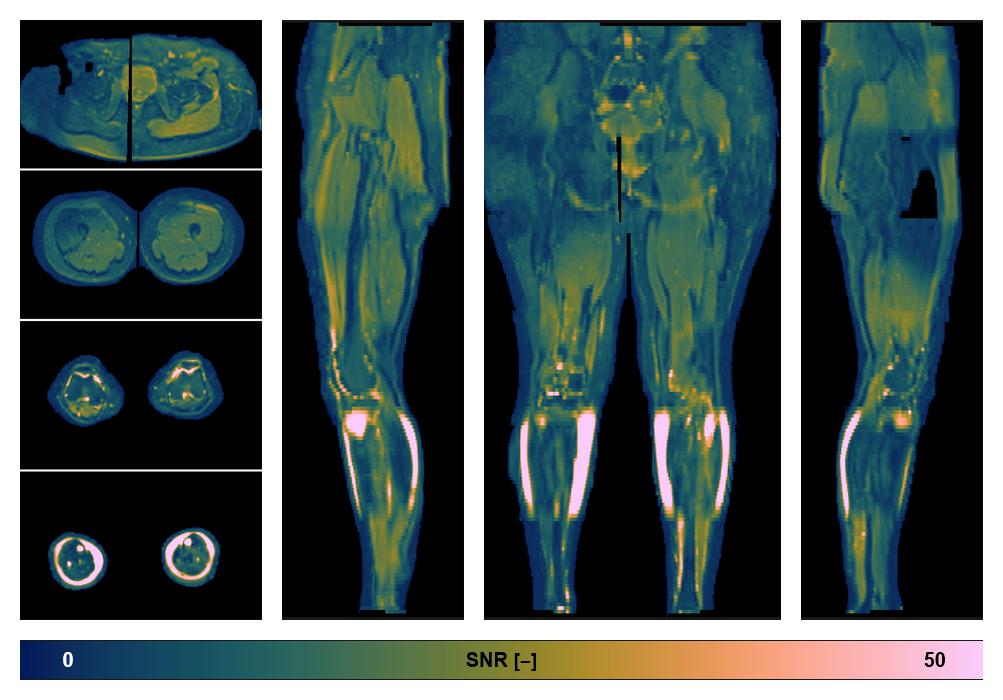

• SNR of the unweighted image

SNR distribution of the unweighted diffusion data.